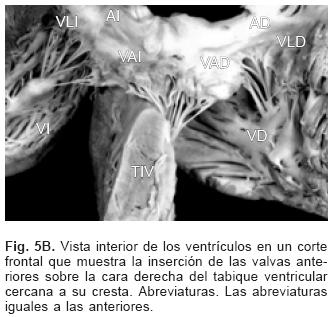

De los sesenta y cinco corazones con válvula común en veinticinco se determinaron los tipos de la clasificación de Rastelli que fueron los siguientes: en once (44%) las valvas anterosuperiores derecha e izquierda se insertaron a través de sus cuerdas tendinosas sobre la cresta del tabique ventricular y la CIV se ubicó en los espacios intercordales (tipo A de Rastelli) (Figs. 1A y 5A). En un espécimen las valvas anterosu–periores izquierda (valva puente) y derecha se insertaron sobre la cara derecha del tabique ventricular por debajo de su cresta (Fig. 5B) y en otro dicha inserción se hizo en la parte superior del cuerpo de la trabécula septomarginal (Fig. 5C). En ocho corazones (32%) la inserción de esas valvas se estableció en un músculo papilar situado en la unión del tabique ventricular con la pared libre del ventrículo derecho y la valva anterosuperior izquierda pasó como puente por encima de la CIV (tipo B de Rastelli) (Figs. 1B y 5D) y en seis corazones (24%) la inserción de las valvas anterosuperior izquierda (valva puente) y derecha se insertaron en un músculo papilar de la pared libre del ventrículo derecho y esta valva se ubicó por encima de la CIV (tipo C de Rastelli) (Figs. 1C y 5E). En los cuarenta corazones restantes no fue posible determinar los tipos de Rastelli debido a que treinta y tres de ellos presentaron doble entrada ventricular (Fig. 6A) dos tuvieron modificaciones anatómicas generadas por la cirugía y cinco por presentar mutilaciones realizadas durante la necropsia. Los cinco especímenes con dos válvulas separadas tuvieron estructura trifoliada dentro de la unión A–V común (Figs. 3B y 6B); la válvula A–V izquierda mostró una valva lateral y dos septales anterior y posterior unidas a la cresta del tabique ventricular, lo que obliteró la CIV (Fig. 6C). La válvula A–V derecha mostró una valva septal displásica, una anterior y una posterior (Figs. 3B y 6B).

En cuanto a la clasificación de Rastelli16 existe en realidad un espectro de grados de inserción de las cuerdas tendinosas de la valva "puente" en la que los tipos A, B y C constituyen los sitios más frecuentes de esa inserción y se debe considerar la existencia de inserciones intermedias entre ellos como se evidencia en el presente trabajo. Los DSA–V presentes en la doble entrada ventricular ya sea izquierda, derecha o a ventrículoúnico,escapan a la clasificacióndeRastelliya que las valvas anterosuperior–izquierda (valva puente) y la anterosuperior derecha están contenidas en una sola cavidad ventricular. En las formas balanceadas de esta cardiopatía la válvula A–V común se conecta a partes iguales con ambos ventrículos. Las formas de dominancia ventricular se expresan cuando la válvula A–V común se conecta preponderantemente con un ventrículo, en la dominancia de tipo derecho el ventrículo izquierdo es pequeño, ya que posee menos superficie valvular, mientras que en la dominancia de tipo izquierdo es el ventrículo derecho el de menor tamaño. En este concepto se consideran las dobles entradas a ventrículo derecho o al izquierdo.30